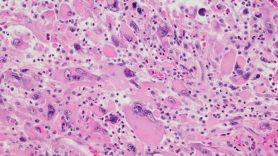

Anaplastic thyroid carcinoma is a rare and highly aggressive malignant tumor with a very poor prognosis. ATC often develops from differentiated thyroid cancer subtypes, such as papillary and follicular thyroid carcinoma, and each subtype has distinct driver mutations that can influence tumor behavior and progression.